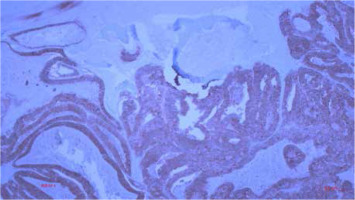

Figure 8

Histological finding of metastatic CRC in the tibia with positive immunohistochemical reaction to CK 20 (100×)